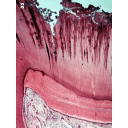

abscesopulpar-2.png